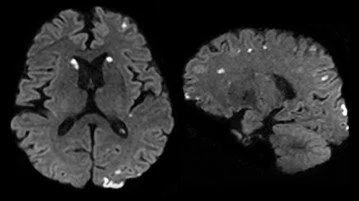

What is SWI?

A multi-echo acquisition sequence with submillimeter resolution and a reconstruction algorithm that provides the ability to clearly delineate small vessels and microbleeds.

Axial DWI

Axial 3D SWI